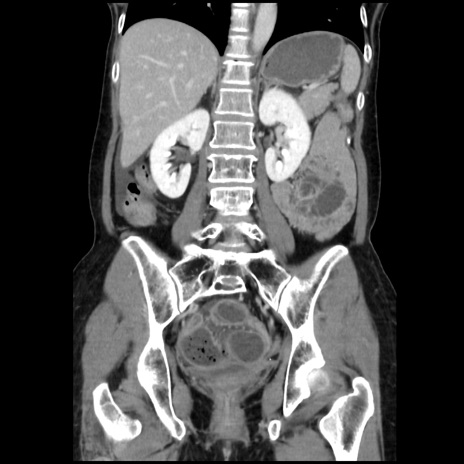

症例32(冠状断像)

【症例】40歳代 女性

【主訴】上腹部痛、嘔気・嘔吐

【現病歴】約9時間前頃から急に上腹部痛、嘔気、嘔吐が出現。改善しないため救急要請。

【既往歴】子宮頚癌(広汎子宮全摘術、放射線療法)、腸閉塞

【身体所見】腹部:平坦、軟、腸雑音亢進、上腹部を中心に腹部全体に圧痛あり。

【データ】WBC 8400、CRP 0.03

横断像